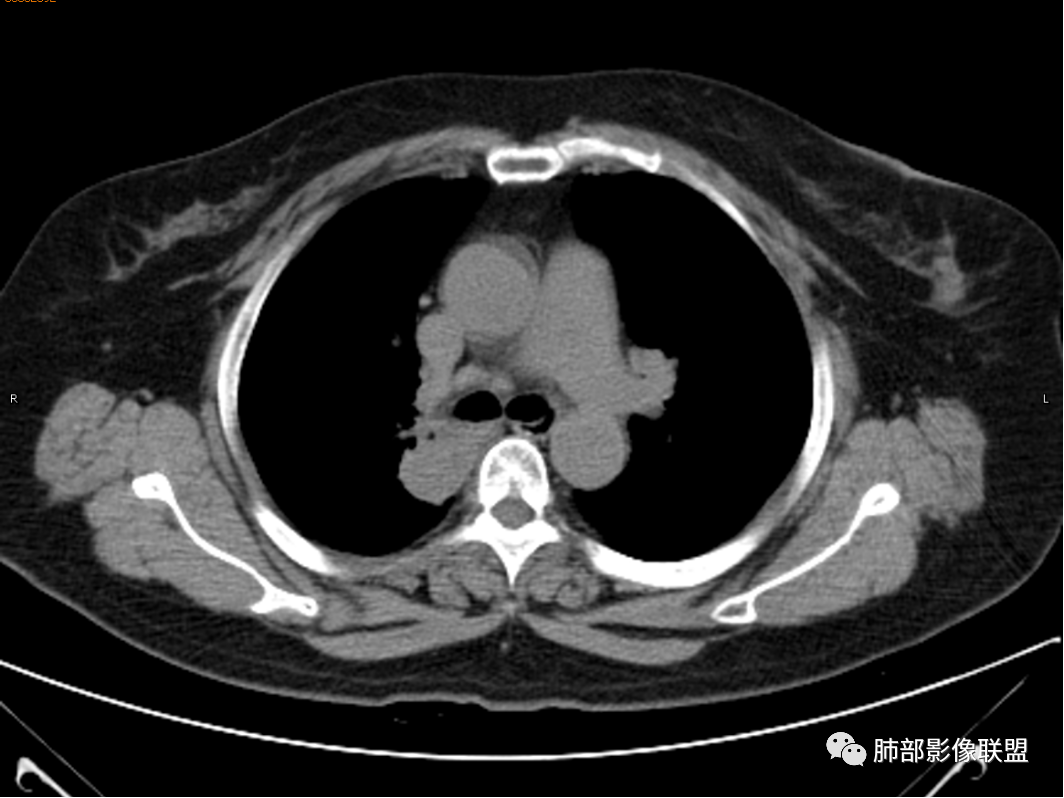

杨丽:老年女性,无肺气肿背景。右肺上叶后段胸膜下肿块,局部浅分叶,边缘见长软毛刺,支气管通入,临近叶间胸膜略增厚,增强扫描可见明显坏死,坏死边界清晰,壁较薄,其余病灶中等强化。纵隔小淋巴结。考虑:感染性病变,结核?鉴别囊肿伴感染。

玫:咳嗽,咳痰,痰中带血一个月,肿瘤标志物不高,右肺上叶肿块影,边界清晰,浅分叶及少许毛刺,增强扫描病灶边缘呈环形强化,病灶内见坏死区,考虑结核可能,鉴别腺癌。

蕊:环形强化,中心性坏死,坏死界线较清楚,肺门淋巴结肿大,考虑结核可能。

薏米:咳嗽,咳痰带血就诊,右肺上叶不规则密度增高影,未见支气管截断,边缘以凹陷收缩为主,环形强化,坏死边界清,坏死比较彻底,考虑结核,鉴别鳞癌、类癌。

王秀仙:右肺上叶后段结节,分叶,部分边缘平直部分膨隆,周围可见磨玻璃晕,密度不均,中心低密度坏死,增强薄环状强化,坏死界线较清楚,纵膈小淋巴结肿大,考虑肉芽肿性病变,结核。鉴别鳞癌。

傅昌瑜:女性,咳嗽咳痰痰中带血1月。血常规、肿瘤标记物正常。CT:右上叶后段类圆形结节,内侧紧贴纵隔,前与右主支气管后壁分界不清。外后部分边缘平直收缩、矢状位可见U型凹陷、桃尖征,周围见边缘模糊的GGO,软毛刺。右上叶后段支气管似乎变狭窄。增强呈薄壁环形强化,内部强化不明显,强化时边缘似见有多个小结节与主病灶融合(芋艿子?)。远端见细小结节。整体考虑炎性病变,结核可能性大,注意鉴别腺癌。

张小兵:坏死为软组织密度44.5Hu,边界清楚,厚薄均匀,符合结核的干酪性坏死。

大雄:平扫 40多 ,是凝固性坏死,所以不支持肺脓肿

赵春杨:右肺上叶后段肿块,部分边缘平直部分膨隆,周围可见磨玻璃晕,密度不均,中心低密度坏死,增强环状强化,坏死界线较清楚,纵膈见多发肿大淋巴结,考虑肉芽肿性病变,结核可能性大,鉴别鳞癌。

1.女性,咳嗽咳痰痰中带血1月。血常规、肿瘤标记物正常。             2.CT示右肺上叶不规则肿块,边缘以平直收缩为主,可见U型凹陷及桃尖征,周围见边缘模糊的GGO,软毛刺,从形态学的角度病灶更支持炎性改变; 3.增强呈薄壁环形强化,壁光整、清楚,也支持炎性改变;病灶内部平扫CT值密度比较高,约40HU,明显高于水的密度,而且未见强化,提示病灶的坏死可能为凝固性坏死;    4.从上面的分析,病变更符合炎性,患者白细胞不高,治疗后没有好转,不支持普通细菌的感染;影像病灶较局限,边界较清楚,病灶慢性炎症或肉芽肿,形态机发病部位更符合继发性肺结核。患者非易感人群,病灶孤立,尽管有液化,也很难第一时间考虑真菌,尤其是曲霉菌感染。什么是炎性肉芽肿?炎性肉芽肿的常见疾病谱系有哪些?那什么是凝固性坏死和干酪样坏死?跟一般的液化性坏死有什么区别?接下来我们逐一学习一下。